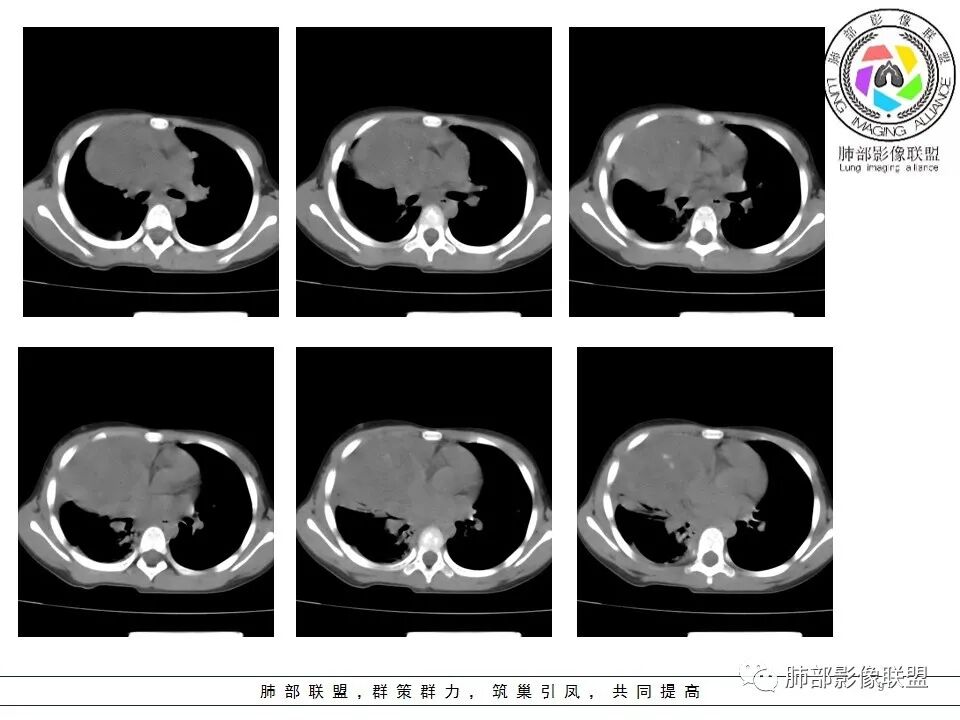

一切∮随缘: 前纵隔偏右侧实性占位,向右肺挤压,右肺膨胀不全,右侧胸水,心包似乎也有胸水,病灶较大无增强,平扫密度欠均匀,内部似可见低密度坏死及高密度钙化影,年轻男性,考虑恶性,生殖细胞肿瘤(精原细胞瘤?恶性畸胎瘤?),鉴别神经母细胞瘤,肺母细胞瘤,PNET?

秦化君: 右前上纵隔软组织密度肿块,边缘部分清晰澎隆,与血管及心包间界线不清,密度较均匀。挤压相邻肺组织形成膨胀不良,侵及胸膜形成胸腔积液。双肺内见随机分布结节。考虑纵隔恶性占位(肺及胸膜转移),生殖细胞瘤,畸胎瘤,淋巴瘤。建议穿刺活检。

放射线 (王秀仙): 右侧前纵膈巨大肿块,与纵膈大血管分界不清并受压,右肺组织受压膨胀不全,密度不均,内可见高密度钙化及低密度坏死区,双肺多发结节状转移灶,右侧胸腔积液,年轻男性,考虑生殖细胞肿瘤,精原细胞瘤可能性大。

不吝慷慨: 小孩儿,首先考虑生殖类肿瘤,双肺胸膜转移,恶性程度非常高,首先考虑精原细胞瘤,鉴别内胚窦瘤,查hcg,AFP和ldh。

宇宙: 男性小孩,右前纵膈不规则肿块,与心脏及大血管分界不清,邻近肺组织受压,其内可见钙化及低密度坏死,两肺多发类圆形结节,右侧胸水,考虑精原细胞瘤伴两肺及胸膜转移,鉴别恶性畸胎瘤。

金豆 (刘权威): 病灶主体位于纵隔,密度不均,内可见点状钙化灶,邻近肺组织受限不张,两肺散在结节,右侧胸水,9岁,恶,生殖类,恶性畸胎瘤,鉴别精原。

放射小白: 男9岁,胸痛,定位右前纵隔占位,内部可见钙化灶,右肺局部实变,两肺散在结节灶,右侧胸腔少量积液,常规考虑生殖类肿瘤,精原细胞瘤伴两肺转移,请结合实验室检查。

空格: 9岁,胸痛10天,胸腔积液,肺内结节,纵膈占位,密度均匀,低于胸腺密度,肺压迫性不张,恶性没问题,小孩子拍死生殖细胞瘤,那个细胞类型,不好说, 绒癌可能大。

良孑: 右侧前纵膈巨大肿块,与纵膈大血管分界不清并受压,右肺组织受压膨胀不全,密度不均,内可见高密度钙化及低密度坏死区,坏死边界不清,双肺多发结节状转移灶,右侧胸腔积液,定性恶性,考虑生殖细胞肿瘤,精原细胞瘤或内脏窦瘤可能性大。

位移: 右侧前纵膈巨大肿块,内可见钙化及坏死区,两肺多发结节状转移灶,右侧胸腔积液,儿童,男,考虑生殖细胞肿瘤,精原细胞瘤可能性大,其次恶性畸胎瘤,外周性原始神经外胚层肿瘤。

蔡磊: 男孩,9岁,胸痛10天就诊。前纵隔偏右侧巨大肿块,内见点状钙化,与周围大血管结构不清,推移挤压。右肺受压,节段性不张。增强后双肺内多发类圆形实性结节。恶性病变肺内转移,生殖可能。

右前纵隔巨大软组织肿块,主要偏向右侧生长,边界不清,密度不均匀,内见大片状低密度坏死区及散在钙化灶,未见骨骼影及脂肪密度影。、双肺随机分布的转移瘤结节,右肺肺不张及右侧胸腔积液,提示恶性肿瘤病变伴双肺及胸膜转移。